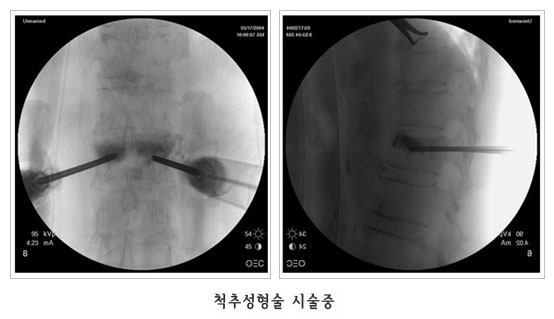

°æÇÇÀû ôÃß¼ºÇü¼ú (Vertebroplasty)

°ñ´Ù°øÁõ¼º ôÃ߾йڰñÀý¿¡¼­ ¼ö¼úºÎÀ§¸¦ ±¹¼Ò ¸¶ÃëÇÑ ÈÄ X-¼± Åõ½Ã±â·Î Åõ½ÃÇϸ鼭, °ñ ½Ã¸àÆ®¸¦ °ñÀýµÈ ºÎºÐ¿¡ ÁÖÀÔÇÏ¿© ôÃß»À ÀÚü¸¦ ưưÇÏ°Ô º¸°­½Ãŵ´Ï´Ù.